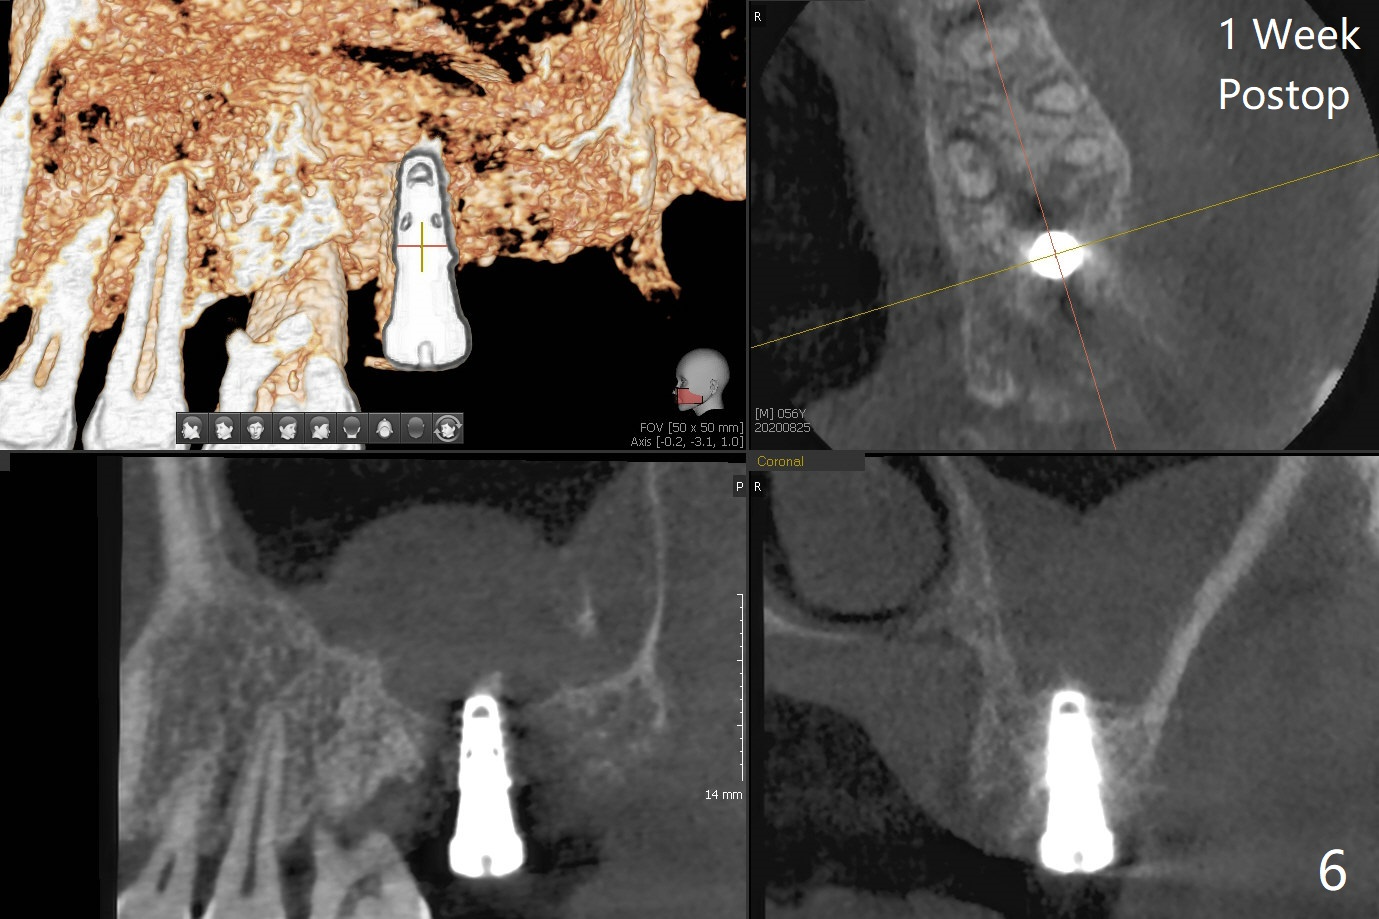

cartridge),植入短小植体(4.5x7毫米,原定(5x8.5毫米)图二),由于稳定性好,使用5.5毫米profile钻头后,放置5.5x4毫米愈合基台(图三)。术后病人没有什么上颌窦不适和分泌物。估计Novo

Bone在上颌窦里凝固了。其实左侧上颌窦粘膜术前增厚(图四,五:L),人工骨仿佛弥撒在上颌窦膜中(图六)。术后一周病人没有任何鼻窦症状。术后4.5月旋转愈合基台时,病人感到疼痛,终止取模(图七),两个月后复诊,做progressive loading。术后5.5月旋转愈合基台时,植体一起出来,但是上颌窦膜没有破,放置大一号植体(报废)扭力不够(图八),再大一号扭力可以(图九),放置愈合帽。由于邻牙长(图九:双箭头),牙周敷料逗留三周不掉(图十:P)。撤除后,伤口愈合正常。The